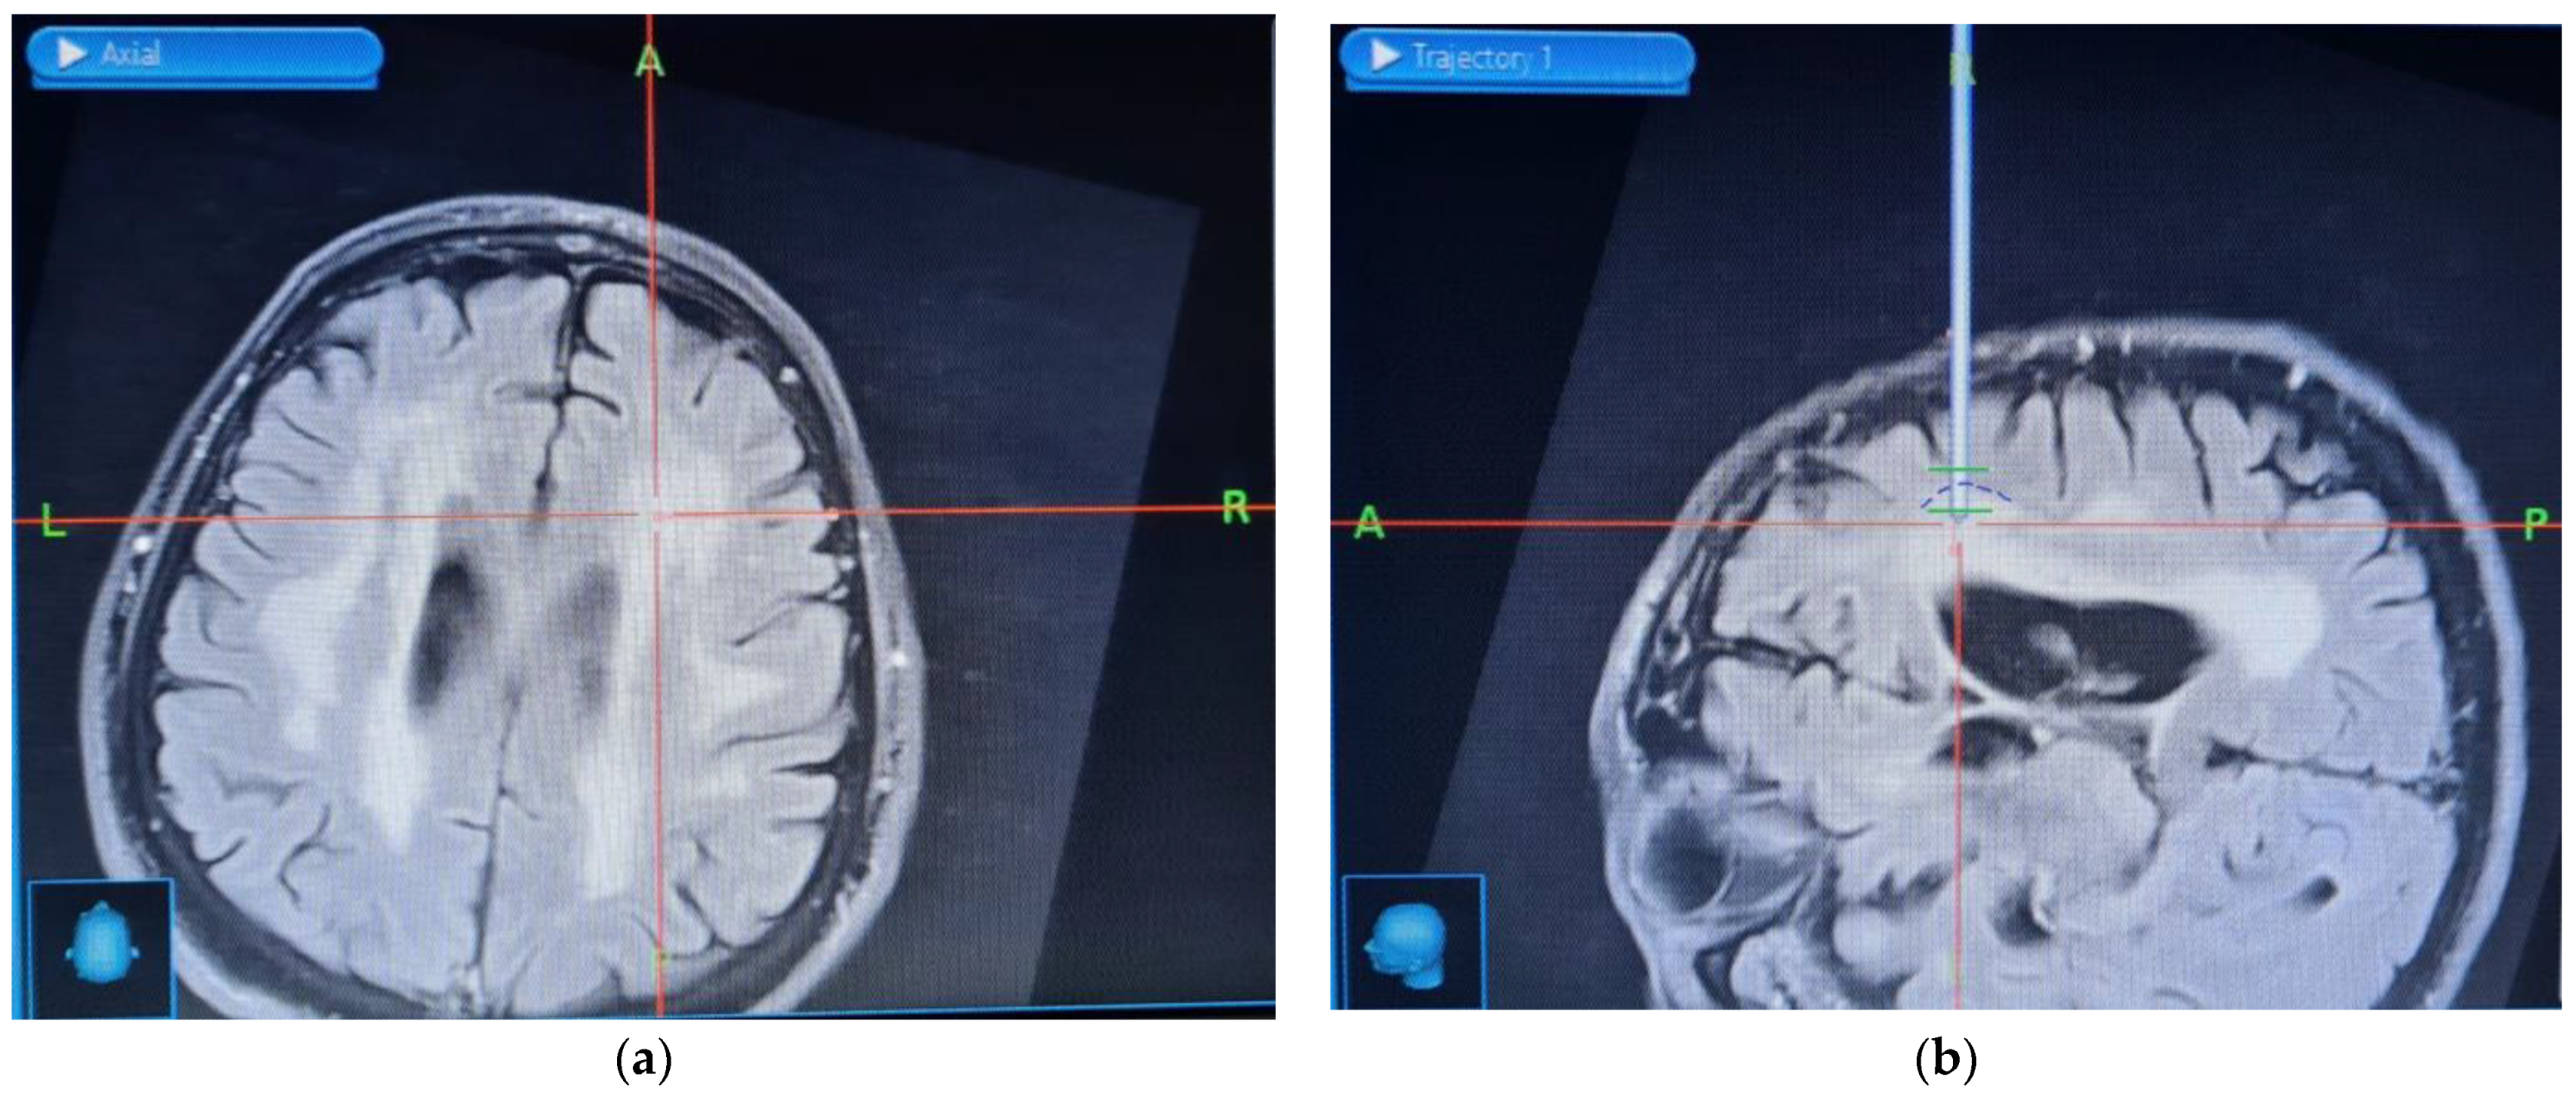

2.2. Patient 2